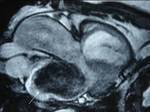

Background: Proper diagnosis of the type and extension of a cardiac tumor or mass is very important for therapy planning. Echocardiography has an established role as a non-invasive diagnostic imaging modality. Computed tomography (CT) and magnetic resonance imaging (MRI) also provide adequate delineation of cardiac tumors and masses.

Methods: Twenty-two patients referred to our department with a suspected cardiac mass, previously detected by cardiac ultrasound, were evaluated by CT (12 patients) and MRI (4 patients). Six patients were examined by both modalities. In 2 cases of staging of a known primary neoplasm and one case of a suspected epicardiac lesion, positron emission tomography (PET-CT) was performed. The CT cardiac examinations were performed using a 16-slice multislice scanner with ECG gating. The MRI examination was performed on a 1.5 Tesla MRI scanner using an ECG-gated cardiac protocol and the PET-CT examination was performed on an integrated PET-CT four-slice scanner, using 370 mMBq of fluorodeoxyglucose.

Results: Twenty-two cardiac masses were successfully detected and their characteristics adequately delineated, including eight myxomas, one angiosarcoma, one ventricular lymphoma, one endocardiac metastasis, one epicardiac paraganglioma, and 10 cases of intracardiac thrombi.

Conclusion: CT and MRI are noninvasive imaging modalities which can delineate cardiac tumors and masses and provide essential information for adequate diagnosis, staging and treatment planning. Compared to cardiac ultrasound, CT and MRI are superior in preoperative planning.